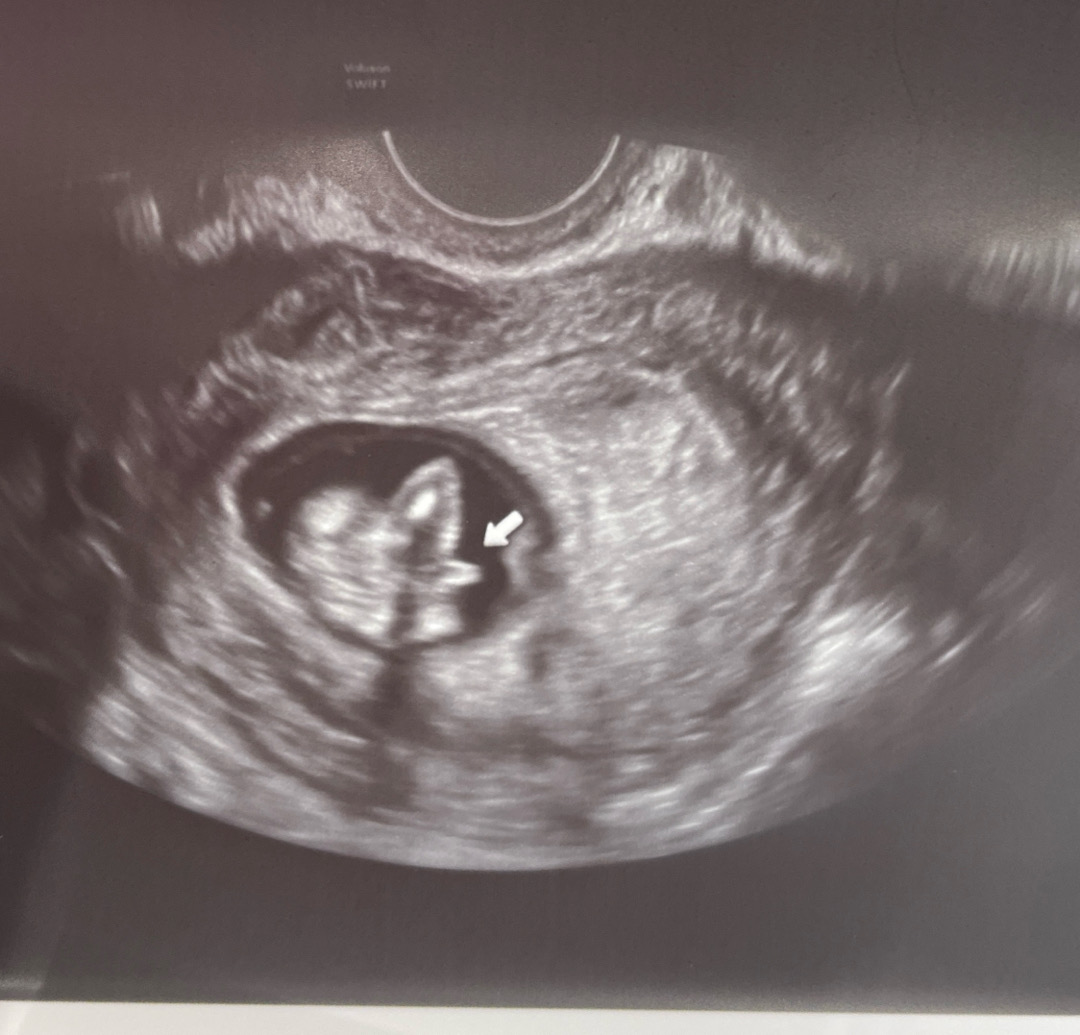

슨생님이 다리 사이라고 찍어주셨는데, 성별 뭐로 보이시나요…? 아직 이르긴 하지만요!

12주까지는 여자애기든 남자애기든 튀어나와있대용! 장꾸맘카페에 각도법 영상 올려보시면 알 수 있으실 거에용 ~.~